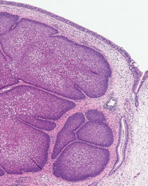

Kırk iki yaşında erkek hasta burun tıkanıklığı ve dolgunluğu şikayeti ile başvuruyor. Hastanın paranazal sinüslerinden biyopsi yapılıyor. Biyopsi materyalinin incelenmesi sonrasında aşağıda resmi verilen lezyon

izleniyor.

Buna göre en olası tanı aşağıdakilerden hangisidir ?

C) Endofitik papillom

CEVAP: C

Resimdeki paranazal lezyonun mukozadan içeriye doğru büyümesi ve papiller yapılar oluşturması nedeniyle öncelikle endofitik papillomu düşündürmelidir. Agresif ve lokal invaziv tiptir. Olguların %10’unda malign transformasyon izlenir. Devrik papillom da denir.